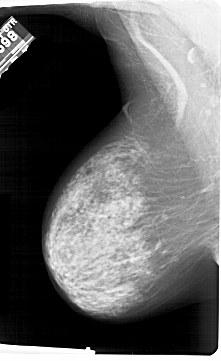

A_1490_1.LEFT_MLO

LEFT_MLO LINES 6856 PIXELS_PER_LINE 4186 BITS_PER_PIXEL 12 RESOLUTION 43.5 NON_OVERLAY

RIGHT_MLO LINES 6871 PIXELS_PER_LINE 4516 BITS_PER_PIXEL 12 RESOLUTION 43.5 OVERLAY

FILE: A_1490_1.RIGHT_MLO.OVERLAY

TOTAL_ABNORMALITIES 1

ABNORMALITY 1

LESION_TYPE CALCIFICATION TYPE PLEOMORPHIC DISTRIBUTION LINEAR

ASSESSMENT 4

SUBTLETY 3

PATHOLOGY MALIGNANT